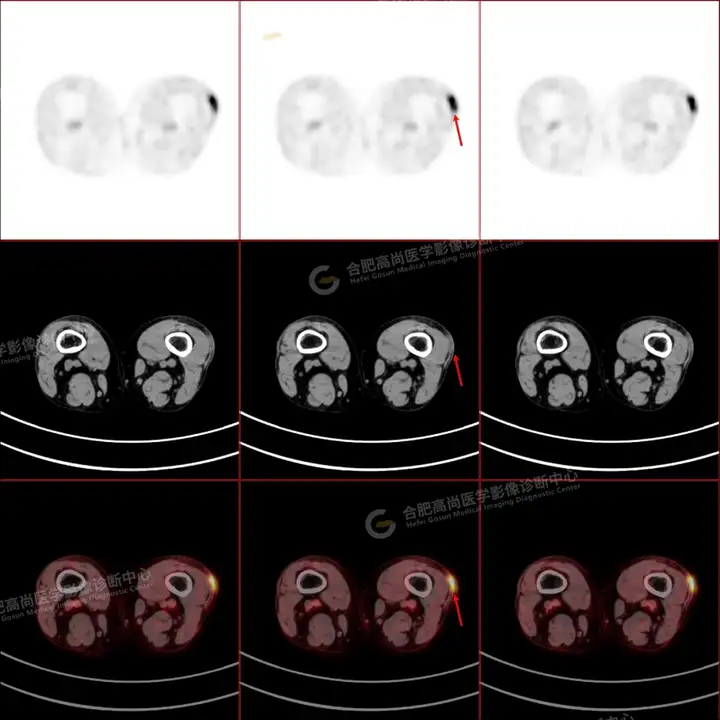

PETCT检查所示:图1、3-17全身多处(双上臂、胸背部、左侧乳腺、左侧腰部、腹壁、双侧臀部及双侧大腿)皮肤下结节及肿块样软组织密度灶,FDG代谢不同程度增高,双侧颈部、左侧锁骨区、纵隔内(1区)及双侧腋窝多发肿大淋巴结,FDG代谢明显增高,符合皮肤来源淋巴瘤。